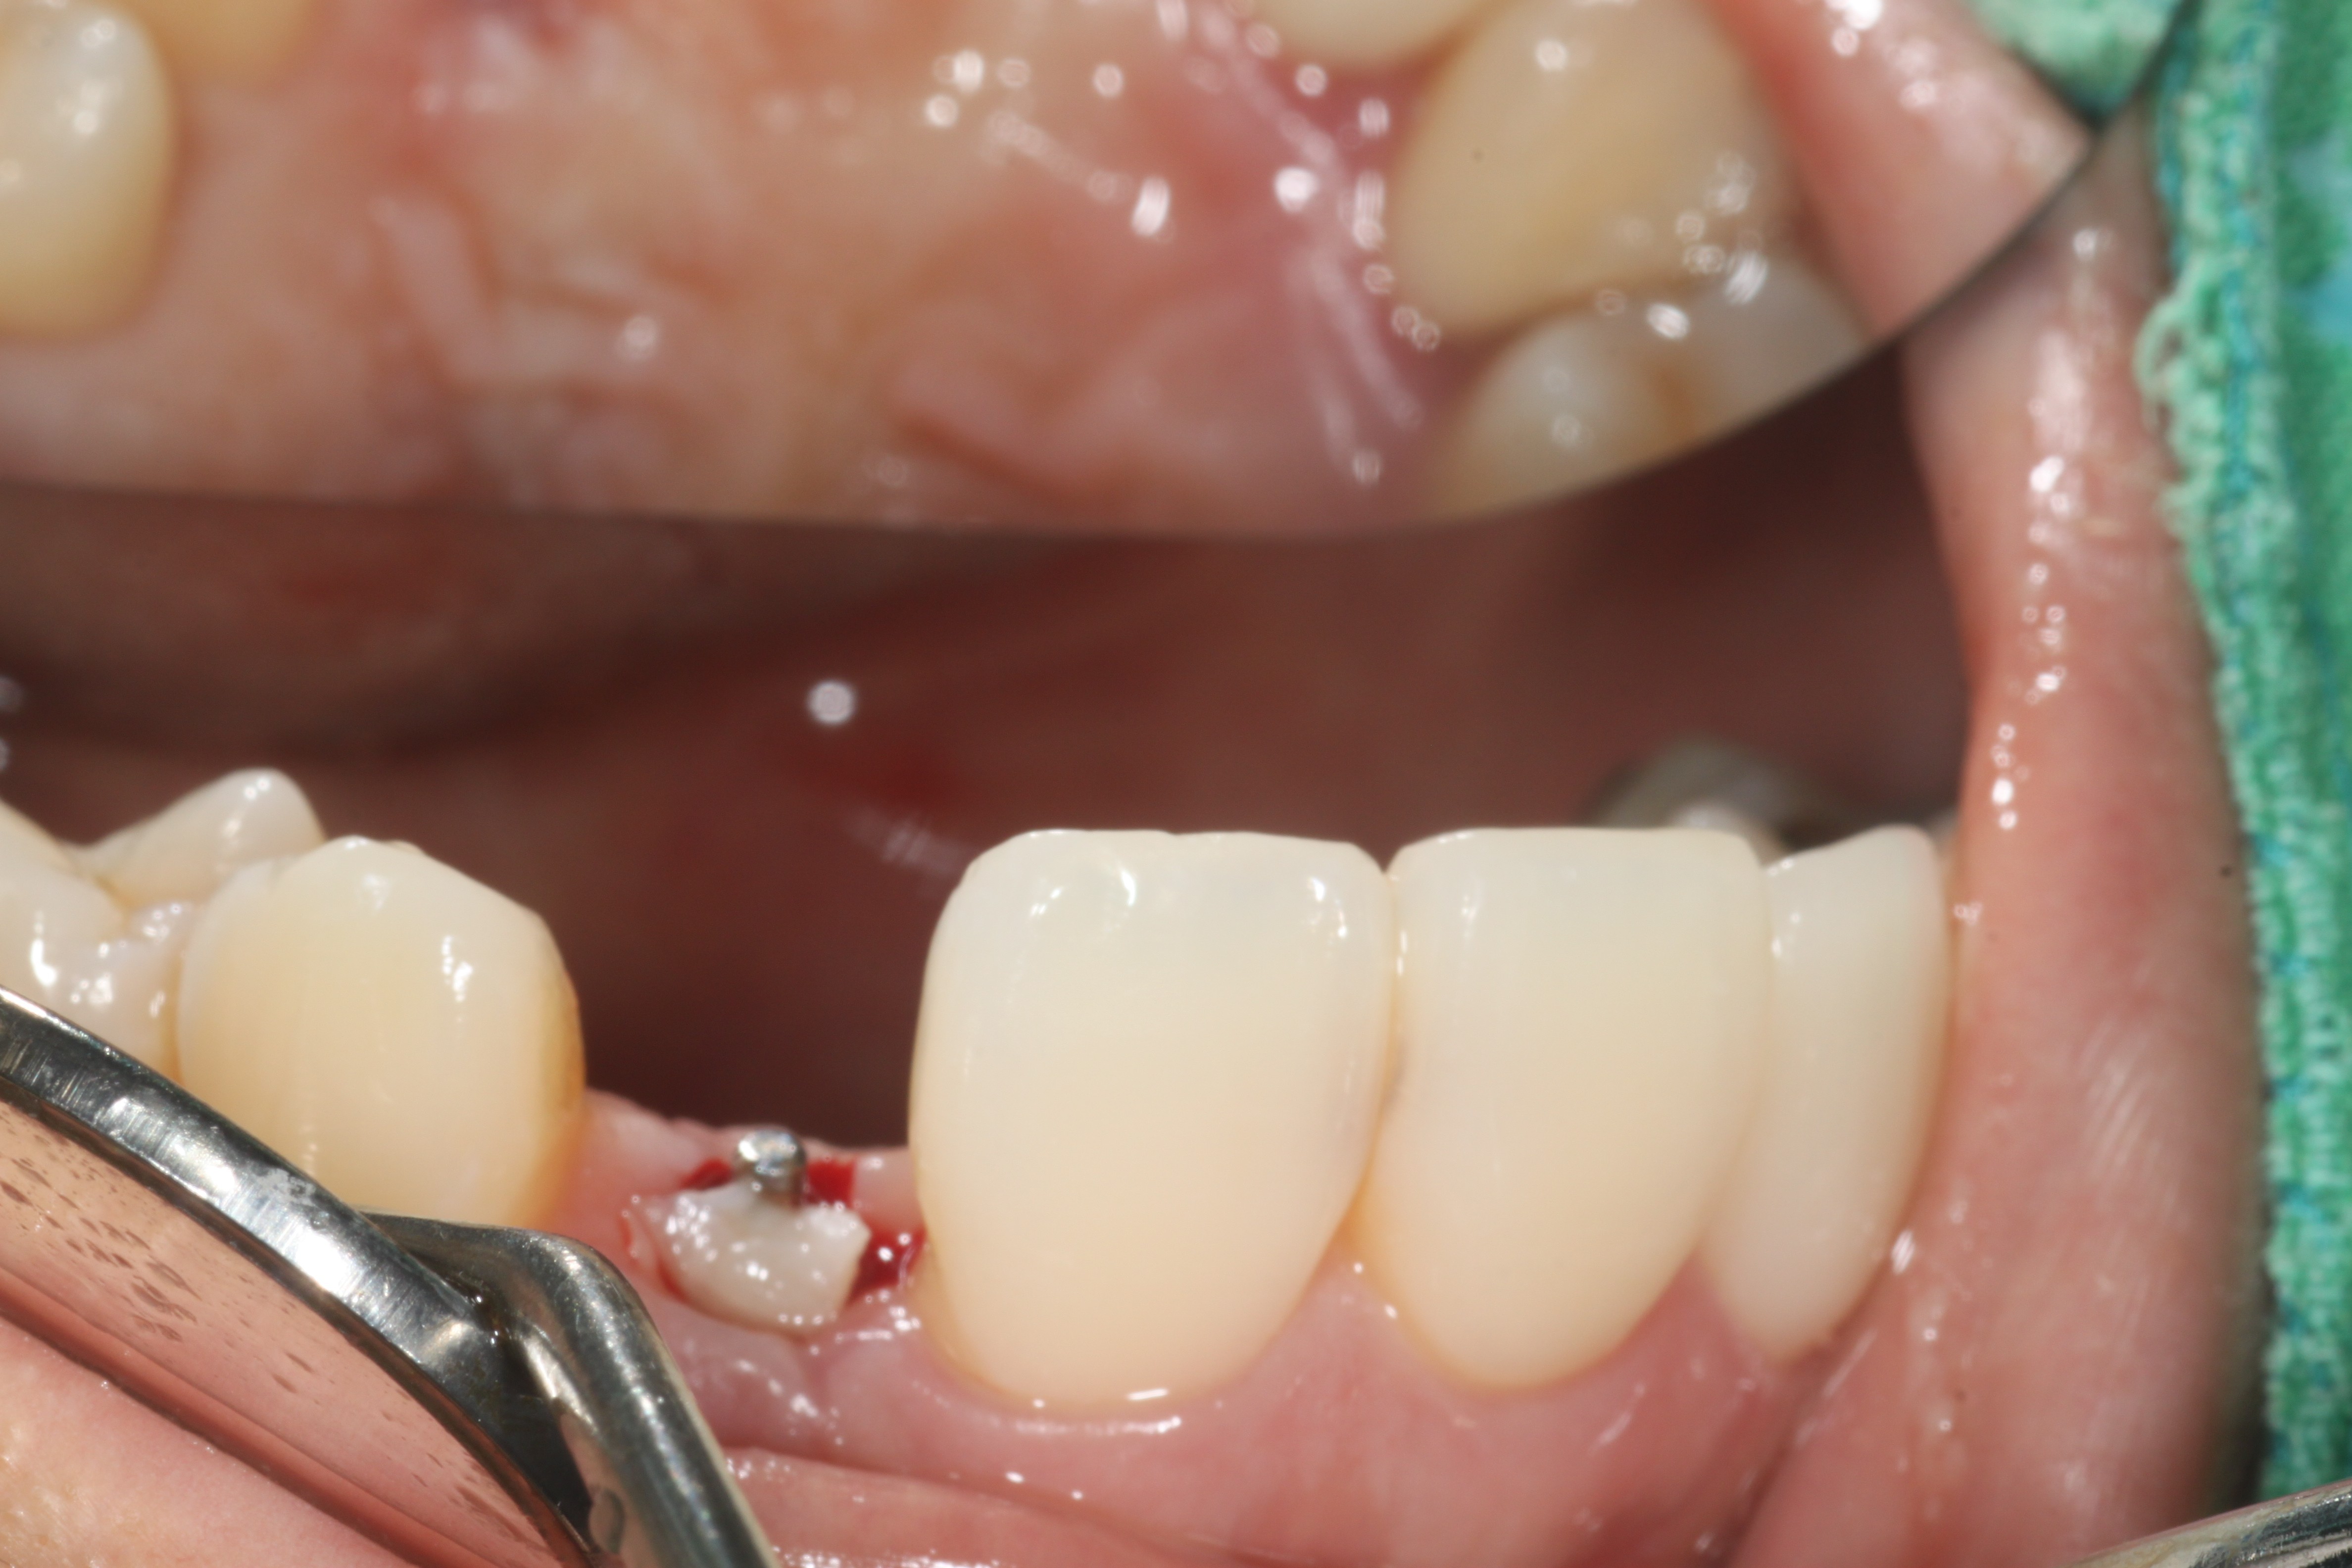

24³â 03 15ÀÏ ÀüÄ¡ºÎ½Ä¸³°í°ú °¡ÀÇÄ¡¸¦ ¸¸µé¾îÁÖ¾úÀ¾´Ï´Ù.

36¼¼¿© ȯÀÚºÐÀÔ´Ï´Ù.1¿ù¿¡ ¸¹ÀÌ Èçµé¸®°í »ÀÀÇ Èí¼ö°¡ ½ÉÇØ °ñÀ̽ĸ¸ ÇØ ³õ°í ÀÕ¸ö°ú °ñÁ¶Á÷À̾î´ÀÁ¤µµ Çü¼ºµÇ¾î ÀÓÇÁ¶õÆ®¸¦ ½Ä¸³ÇÏ¿´À¾´Ï´Ù.